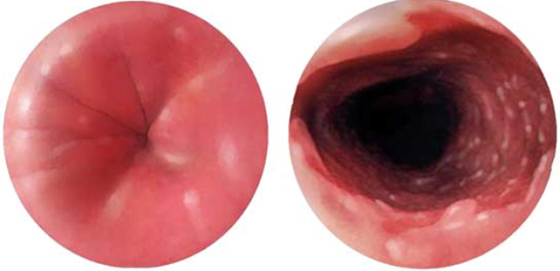

QB-nun epifrenik divertikulu

Pulsion, yalançı divertikuldur. QB-nun distal 10 sm hissəsində, aşağı sfinkterin üstündə yerləşir. Kiçik divertikullar adətən əlamətsiz olur, böyük divertikullar isə disfagiya, divertikulit və fistul törədə bilirlər.

Etiopatogenez

Qazanılmış xəstəlikdir. Əmələgəlmə mexanizmi Zenker divertikuluna bənzərdir. Axalaziya, diffuz spazmlar, hiatal yırtıqlar və strikturlarda mənfəzdaxili təzyiqin artması hesabına divertikul formalaşır.

Diaqnostika

Dəqiqləşdirmə

Diaqnozun dəqiqləşdirilməsi üçün kontrastlı şüa diaqnostikası üsulları (Rh-qrafiya və ya KT) və endoskopiya aparılmalıdır.

- Kontrastlı Rh-qrafiya - dəqiqləşdirici müayinə üsuludur.

- Endoskopiya - divertikulun perforasiyası təhlükəsinə görə çox ehtiyatla aparılmalıdır. QB-nun xəstəliklərinin və paraezofageal yırtıqların diferensiasiyası üçün mühümdür.

- Manometriya - divertikulun səbəbini (axalaziya, diffuz spazm, “fındıqqıran” QB) aşkar etmək üçün aparılan ən vacib müayinə üsuludur.